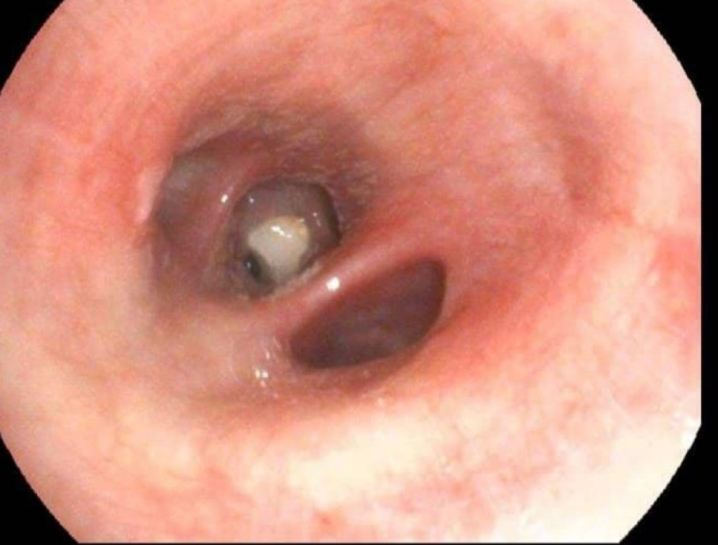

Медики з'ясували, що частина зуба опинилася у легенях під час пологів, які відбувалися шляхом кесаревого розтину. Під час екстреної процедури він відколовся.

За допомогою ендоскопічного кошичка фахівці Центру легеневого здоров'я його видалили, застосувавши місцеву анестезію. Стан жінки значно покращився.